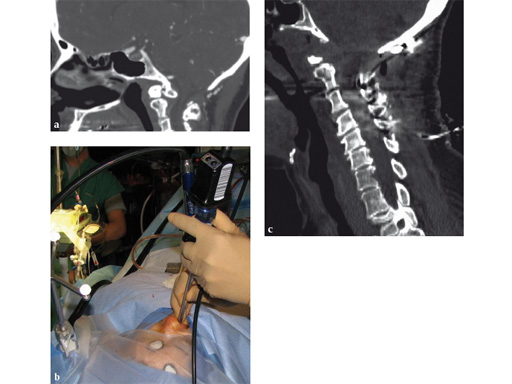

Fig 7ac a Preoperative CT scan: os odontoideum with compression of cervicomedullary junction in a symptomatic patient.

b Intraoperative view of navigated endoscope entering nose. Reference array for navigation has been attached to skull clamp.

c Postoperative CT scan: complete resection of the mass. Patient also underwent occipitocervical instrumentation and fusion.